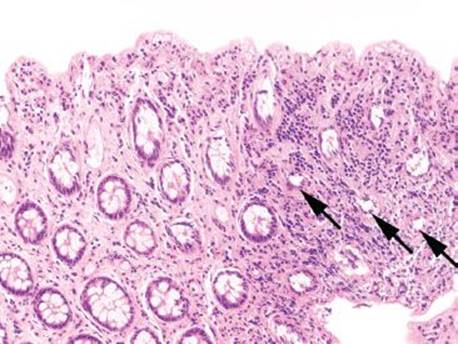

Figure 4.54 Ischemic colitis pattern, withered crypts. Crypt epithelium becomes damaged and sloughs, giving a “withered” appearance to the crypts (arrowheads). Compare these withered crypts to the right side of the photo, which are better preserved.

Decreased blood flow and lack of oxygen to the GI tract result in necrosis or tissue damage, causing ischemia. There are several weak points in the colonic blood supply, known as watershed areas, which result from incomplete anastomosis of the marginal arteries and lack of sufficient collateral circulation. These watershed areas are more vulnerable to ischemic injury than other parts of the colon and include the splenic flexure (or Griffith’s point), the rectosigmoid region at Sudeck’s point, and the ileocecal region. Among the older population, ischemic disease is typically attributable to atherosclerotic mesenteric vascular disease, but the causes of colonic ischemia are many (Table 4.2). The histologic findings are dependent on the timing of the ischemic event (Figs. 4.52–4.63). Early and minimal injury, for example, occurs first as degeneration and sloughing of superficial epithelial cells, edema, and vascular congestion. Later, the epithelial cells become markedly attenuated and the crypts appear compressed and atrophic (“microcrypts”) as the lamina propria swells and hemorrhages. Within 5 hours of total acute vascular occlusion, almost the entire intestinal wall appears necrotic. These changes are devoid of acute inflammation until reperfusion occurs. Paradoxically, reperfusion further injures the tissues by introducing oxygen free radical formation,16 the severity of which is dependent on the duration of the preceding hypoxia.